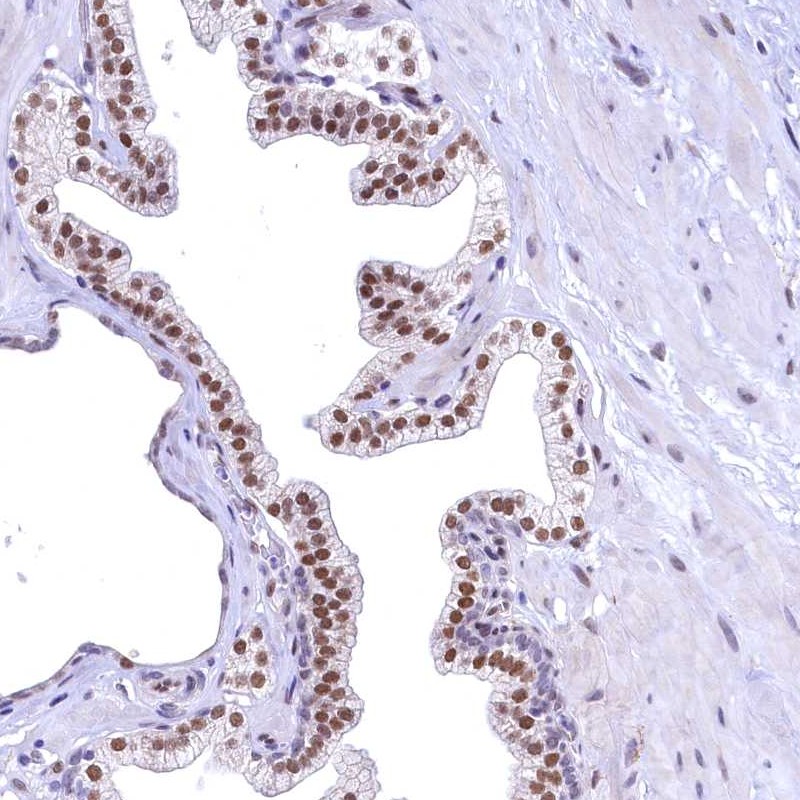

Immunohistochemical staining of human prostate shows moderate nuclear positivity in glandular cells.